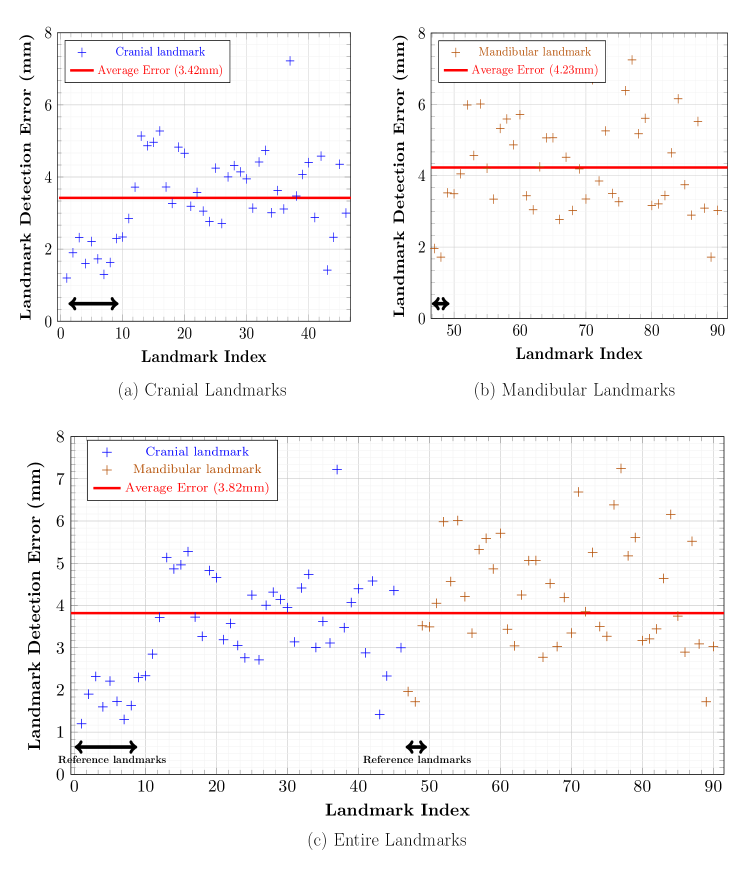

For each landmark, Figure 6 shows the performance evaluation achieved using 9 test data with respect to the averaged 3D point-to-point error. The mean detection error was 3.42 mm for the cranial landmarks (Figure 6(a)), 4.23 mm for the mandibular landmarks (Figure 6(b)), and 3.82 mm for all landmarks (Figure 6(c)). The error of the cranial landmark estimation was much smaller than that of the mandibular landmark estimation.

The human skull morphology follows certain patterns and the positions of landmarks are closely interrelated. To learn a low dimensional representation that is strongly associated with the factors determining skull morphology, the proposed method adopted VAE. In our empirical experiment, as shown in Figures 6(a) and 6(b), the VAE-based approach provided more accurate results for the cranial landmark detection due to the rigid property of the cranium compared to the mandible, which has large shape variance. Among the cranial landmarks, the positional estimation of the SC obtained from the relation learned via VAE exhibited the lowest accuracy (see Figure 8). This appears to have occurred because the summit position of the cranium (SC) may weakly depend on the positions of other landmarks. A rigorous factor analysis using VAE may be provided in future research.